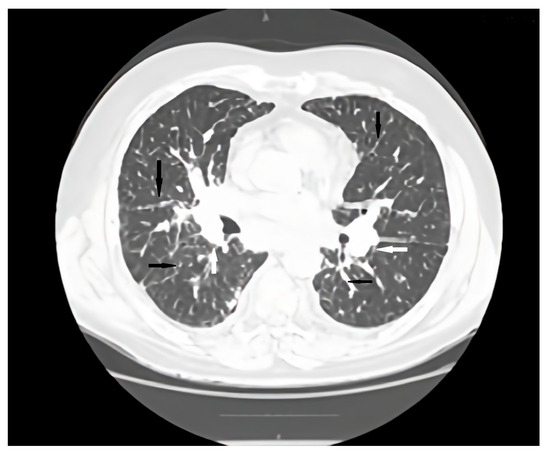

Association Between Common Variable Immunodeficiency and Pulmonary Amyloidosis: Review

by Cristina Maria Radu, Irena Nedelea, Vlad Andrei Ardelean, Adriana Parau and Milena Adina Man

J. Clin. Med. 2026, 15(4), 1446; https://doi.org/10.3390/jcm15041446 - 12 Feb 2026

Background: Common variable immunodeficiency (CVID) is the most frequent symptomatic primary antibody deficiency, associated with recurrent infections, immune dysregulation, and non-infectious complications. Amyloidosis is a rare but severe complication with pulmonary involvement being exceptional. Objective: The aim of this study was to review [...] Read more.

Background: Common variable immunodeficiency (CVID) is the most frequent symptomatic primary antibody deficiency, associated with recurrent infections, immune dysregulation, and non-infectious complications. Amyloidosis is a rare but severe complication with pulmonary involvement being exceptional. Objective: The aim of this study was to review reported cases of amyloidosis complicating CVID and present a unique case of pulmonary involvement. Methods: A literature research identified observational studies and case reports linking amyloidosis with CVID. Additionally, we describe a patient with CVID complicated by pulmonary and gastrointestinal amyloidosis. Results: Fifteen cases were identified, mostly amyloid A (AA) with multiple organ involvement. Only one case of pulmonary amyloidosis was reported. To date, no cases of pulmonary light-chain amyloidosis (AL) have been described in CVID patients without an underlying plasma cell dyscrasia. Our patient initially presented with AA amyloidosis but evolved to systemic AL type with rapid progression and fatal outcome despite therapy. Conclusions: Amyloidosis should be considered in CVID patients with atypical symptoms. Accurate amyloid typing is essential as treatment differs between AA and AL types. Early recognition may improve outcomes. Full article

Show Figures

Figure 1